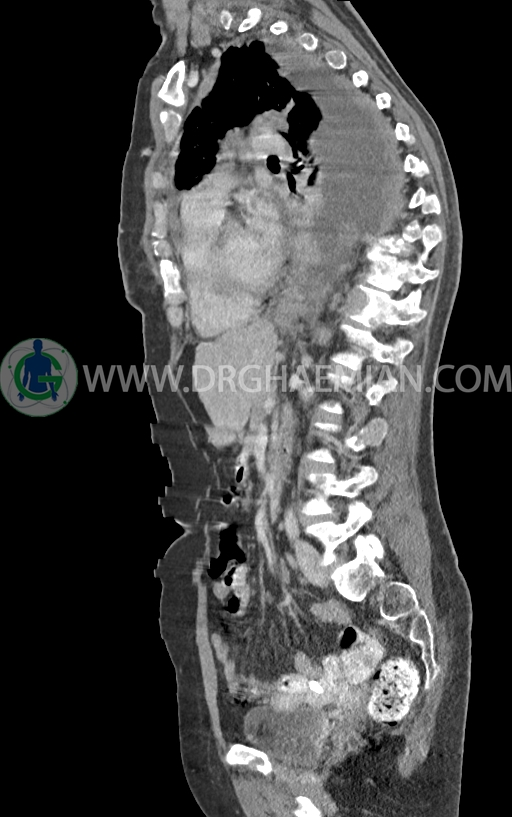

در سی تی اسکن اسپیرال ریه و مدیاستن -شکم و لگن با کنتراست خوراکی و وریدی (مولتی دیدکتور 16 با مقاطع ظریف و بازسازی های ساژیتال و کرونال) :

–ضایعات استخوانی لیتیک فراوان منتشر در تمامی طول ستون مهره و لگن رویت شدند که مطرح کننده متاستاز استخوانی می باشند.

–شکستگی پاتولوژیک در مهره های T6 , T10 , T11

–کیفوز موضعی در Level T10 , T11 در ستون مهره

–رتروپالشن شکستگی مهره T10 همراه با ایجاد تنگی کانال نخاعی

–توده نسج نرمی بسیار بزرگ به حداکثر دیامتر 82mm همراه با مارژین لبوله در پستان راست دیده شد که همراه با گسترش و درگیری پوست و نیپل بوده و مطرح کننده ضایعه تومورال و بدخیم می باشد.

–این توده در قسمت هایی عضله پکتورالیس این سمت را abut کرده است.

–افزایش ضخامت نسج نرمی و ندولاریته در پلور مدیال ریه چپ یا شاید مربوط به قسمت پره واسکولار مدیاستن با حداکثر ضخامت 10mm در level سوپراهیلار چپ دیده می شود که می تواند مشکوک برای لنفادنوپاتی یا متاستاز باشد.

–لنفادنوپاتی در هیلوم چپ وفضاهای مدیاستن دیده می شود بزرگترین آن ها با SAD=11mm در پره تراکئال دیستال و SAD=14mm در هیلوم چپ و 11mm در ساب کارینا دیده شدند

–پلورال افیوژن وسیع دو طرفه